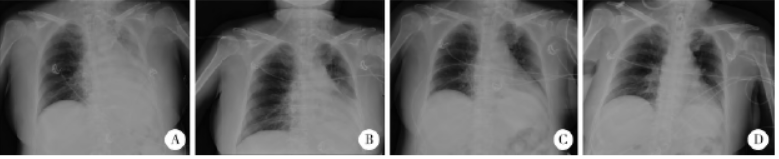

介入栓塞治疗肺吸虫感染性颅内动脉瘤一例

病史摘要:27岁男性患者,主诉“反复发热、咳嗽、咯痰3个月伴突发头痛3d”。既往半年前有生吃溪蟹史。诊疗过程:入院查体意识清楚,无皮下结节,双下肺叩诊浊音,颈强直。急诊头部CT示蛛网膜下腔出血。住院后全脑DSA示右侧大脑中动脉末端动脉瘤;胸部CT示双肺感染等;实验室检查血清肺吸虫IgG抗体阳性,血常规嗜酸性粒细胞比例升高等。诊断为感染性颅内动脉瘤肺吸虫病。行右侧大脑中动脉M4段动脉